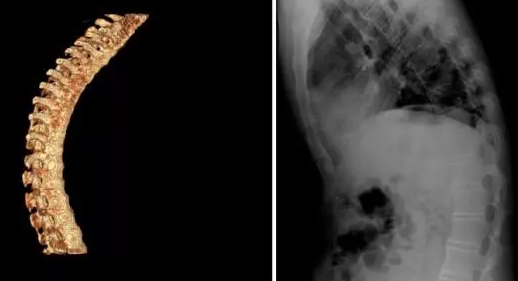

其实不能“断根”并不等于绝症,贵阳治疗强直医院表示很多疾病虽然是不能“断根”的,但却是可以控制的。但经过正规治疗,多数早期的强直患者都可以做到脊柱不融合、不累及内脏,不驼背,股骨头不坏死,可以像健康人一样的工作和生活。

对于强直性脊柱炎中期的患者(主要疼痛、僵直明显,但脊柱弯曲不明显、骨质破坏不严重的患者)60%-80%的经过积极治疗、坚持关节锻炼,可以达到临床缓解或治愈,即疼痛或晨僵消失、血沉或C反应蛋白等炎症指标正常。

对于强直性脊柱炎晚期患者而言,控制病情进一步发展,避免残疾瘫痪是首要任务!控制症状的持续发展,疼痛加重、活动受限的持续加重,保障强直患者生活质量。